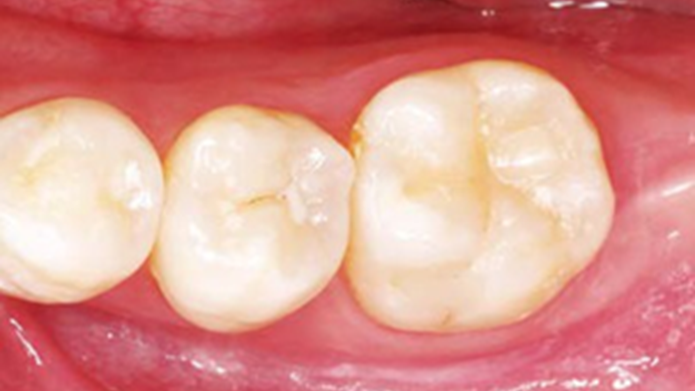

Clinical case: Single molar implant with bone augmentation

- Courtesy of Dr. Jung Sam Lee, Korea -

AnyOne, bone augmentation, osteotomy socket, peri-implant tissue, autogenous bone, GBR, single replacement, Auto-Max, Dr. Jung Sam Lee

AnyOne implant system, Auto-Max